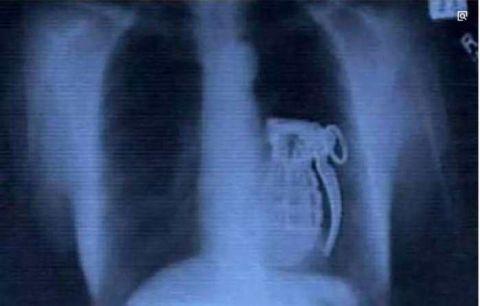

恐怖分子走投入路的时候想要吞下*雷手**同归于尽,结果发现吞下去不能拉环了